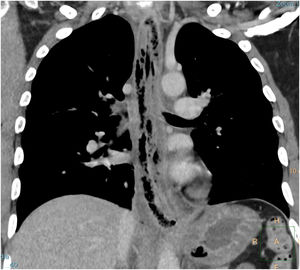

A 49-year-old man from Bolivia consulting for oropharyngeal discomfort with progressive dysphagia, rhinolalia, burning chest pain, and fever of 39 °C. Chest CT scan (Fig. 1) showed severe oesophageal thickening with transmural air bubbles without free air in the mediastinum. Fibrogastroscopy revealed oesophageal oedema along its length to the cardia with no mucosal lesions. Rhinolaryngoscopy described arytenoiditis. Admitted to ICU with broad-spectrum antibiotic and antifungal treatment. Serology was negative. Ten days after admission, radiological improvement (Fig. 2) and clinical stability allowed progressive oral diet to be started without incident. The patient was discharged without a definitive diagnosis.